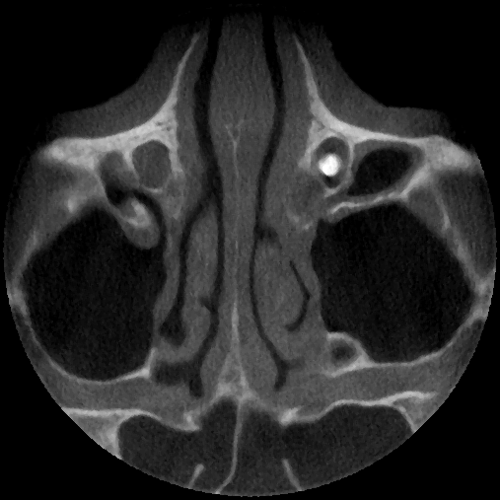

Praesaccale Tränenwegstenose